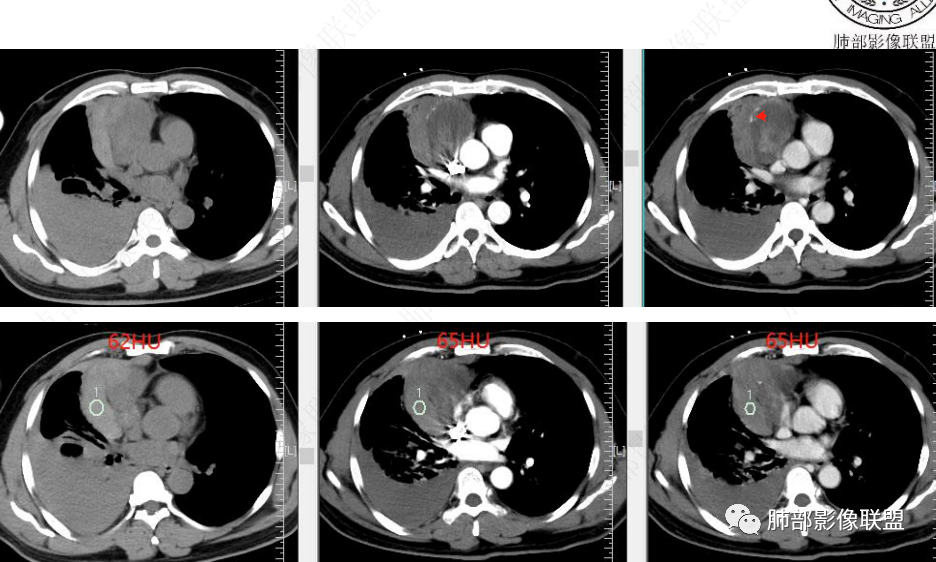

2、CT图像所见:前中纵隔肿块,偏于右侧生长,平扫及增强扫描见肿块形态欠规则,密度欠均匀,内部见低密度坏死区,实性部分及分隔可见轻中度渐进性强化,内部可见细丝状、短条状明显强化小血管影,肿块外侧见弧形高密度无强化影(其与纵隔肿块间脂肪间隙清晰),考虑为出血;右肺中上叶含气不良。右侧胸腔见高密度积液,从平扫到增强扫描短时间量明显增加,符合急性出血。肺窗见双肺胸膜下多发结节,右肺大片状磨玻璃影,左肺下叶磨玻璃结节。

3、综合分析:本例右前上纵隔肿块,内部坏死,实性部分中度渐进性强化,内部可见细丝状明显强化小血管影。肿块与周围血管分界尚清楚,周围脂肪间隙显示不清,邻近胸膜显示增厚,结合瘤体内出血,破入或渗入右侧胸腔,双肺胸膜下结节影,符合恶性肿瘤转移。

临床突发症状与出血相吻合。